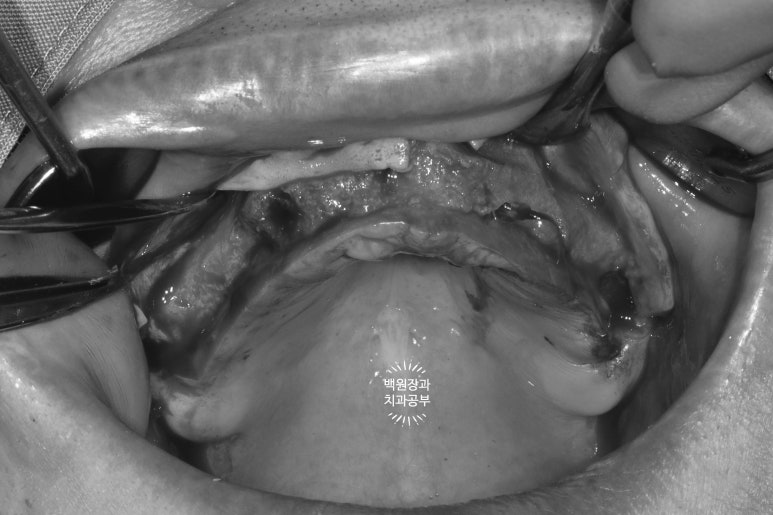

가장 먼저 잇몸뼈의 두께를 확인해야합니다.

CT가 틀릴리 없습니다... 상당히 얇은 잇몸뼈를 관찰할 수 있습니다.

많은 치과에서 절개 없는 임플란트 수술을 한다고 홍보하고 있으나, 이렇게 extreme 하게 많은 뼈이식을 하는 케이스들은 잇몸 절개가 당연히 필수입니다.

수술 시 충분한 절개가 이루어져야 효과적인 잇몸뼈 이식이 가능하고, 임플란트를 좌우 대칭으로 심어드릴 수 있습니다. 고려사항이 상당히 많은 전체임플란트이니만큼, 가능하면 네비게이션 임플란트 수술이 가능한 곳에서 치료 받기를 권해드립니다.

왼쪽 위 잇몸뼈가 상당히 얇음을 역시나 확인할 수 있었습니다.

폭이 약 2-3mm 정도로.. 직경 3.5mm 임플란트를 심을 수 없을 것만 같은 곳이었죠.

이론적으로 3.5mm 임플란트를 심으려면 약 7.5mm 폭의 잇몸뼈를 만들어내야하니 참 곤란한 상황입니다.

오른쪽 위는 그래도 조금 나았던 것으로 기억...

상악동 뼈이식술도 넉넉히 많이 해드려야 했기 때문에, 앞서 언급했던 것처럼 충분한 잇몸 거상이 필요한 상태였습니다. 좋은 시야는 좋은 수술 결과를 만들어내는데 큰 도움을 줍니다.

잇몸뼈가 너무 얇다보니, 임플란트를 위치시키면 이렇게 임플란트의 일부가 드러날 수 밖에 없었고, 이제 어렵디 어려운 잇몸뼈이식이 기다리고 있는 상황..